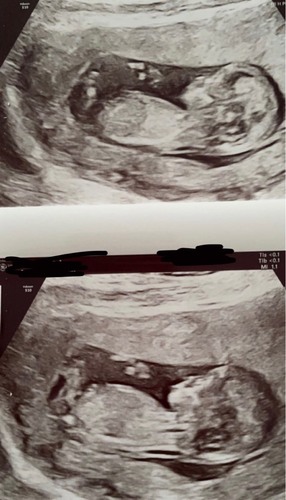

Iemand enig idee wat we hier zien? 💙💗 gisteren mijn 13 weken echo gehad! Ben zo mega benieuwd! Een klein gokje is altijd leuk, 10 februari de geslachtsecho